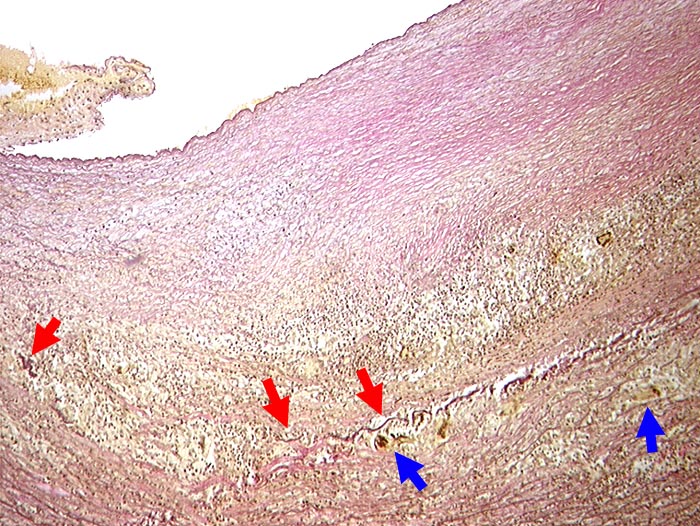

Riesenzellarteriitis der Arteria carotis interna

Dichtes lymphohistiozytäres Entzündungsinfiltrat in Media und Adventitia. Riesenzellen phagozytieren die bereits fragmentierte Lamina elastica externa.

Primäre Vaskulitis mit Befall grosser Gefässe, bevorzugt extrakranielle Äste der Arteria carotis. Temporalarterie häufig betroffen.